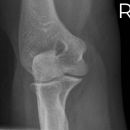

Radiusköpfchen

Kann der Patient den Arm nicht voll durchstrecken, so kann diese Aufnahme auch in Beugung aufgenommen werden, dabei liegt der Unterarm auf (Hand in Supination) z.B. bei Gipskontrolle. -> Greenspan-Aufnahme.

Qualitätskriterien

Orthograde, überlagerungsfreie Abbildung des Radiusköpfchen, freie Darstellung der Articulatio humero-ulnaris